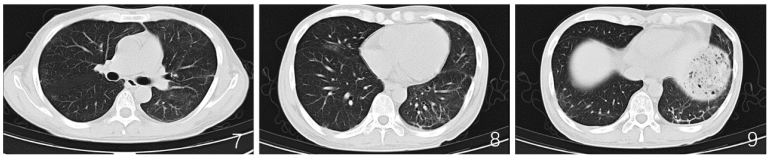

患者病情变化快,经短期治疗后复查影像明显吸收。各项感染及NGS检测均不符合临床表现,病情疑难。再次询问病史,患者近期有明显口干及眼干,吞咽时需饮水,伴腹泻等不适。

查体见口腔舌部有类苔藓样改变,口唇黏膜出现破损、脱屑样改变,咽后壁多发滤泡(图4。完善唾液分泌试验:0.5 ml/15 min。泪液分泌实验(Schirmer试验):左眼3 mm/5 min,右眼5 mm/5 min。

4  患者口腔黏膜改变,可见舌苔苔藓样改变,咽后壁多发滤泡

我所陈荣昌教授查房后认为:①cGVHD高发时间窗多为移植后6个月[1],与患者发病时间相符;②CT可见左下肺牵拉性支气管扩张,符合cGVHD肺部影像学表现[1];③患者反复病原学检查均为阴性,未找到明确病原学证据,感染可以诱发cGVHD但难以解释整个临床过程;④肺组织病理提示机化性肺炎;⑤经激素治疗后短期复查CT见肺部病变吸收明显,亦不支持感染性疾病。综上,考虑患者慢性移植物抗宿主病诊断成立